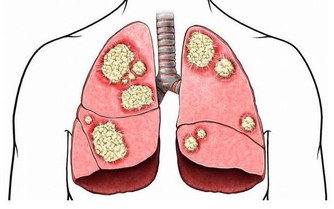

這句話講的是什麼意思呢?頸七椎向下相連的是胸椎的一椎、二椎,這兩個椎體與肺相通,是通往肺的通路,當頸椎扭傷一定牽連到胸椎的一、二椎;腰椎向上相連的是胸十椎、十一椎、十二椎,十一椎、十二椎與脾、胃相通,是通往脾胃的通路,當腰椎扭傷一定牽連到胸十、十一椎。

頸椎下端和腰椎上端的這些部位,往往是在臨床中被遺忘的角落,所以,既影響頸、腰椎的治療,也影響與之相連病症的治療效果。醫者在治療頸椎腰椎的同時,一定要檢查鄰近胸椎椎體的排列狀態,頸椎的治療要注意到肺(胸一、二椎),腰椎的治療要注意到胃(胸十、十一椎),這是治療頸椎腰椎病症的關鍵。